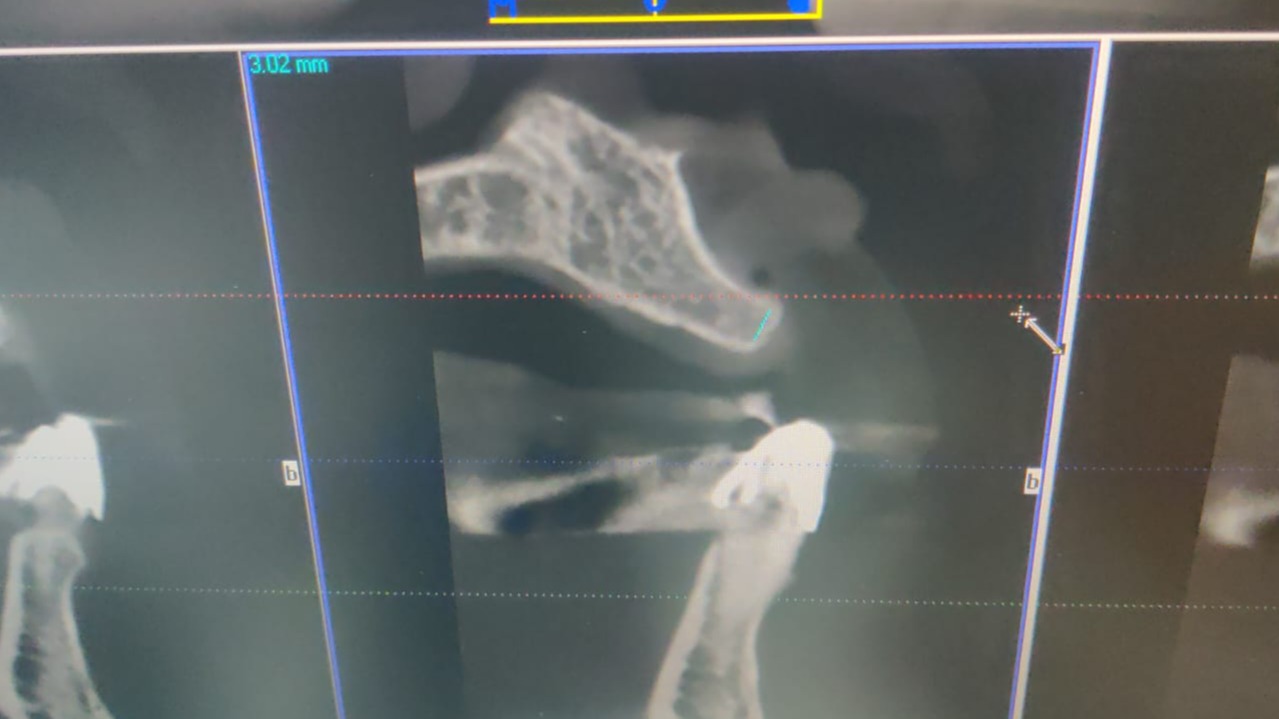

CASE BY DR. SMIJAL -- PRE OPERATIVE CBCT

3 mm width with unfavorable angulation.  In prosthetics angle abutment needed with tall and unaesthetic crown.

CASE BY DR. SMIJAL --NARROW RIDGE

Drilling in this situation will create disaster .